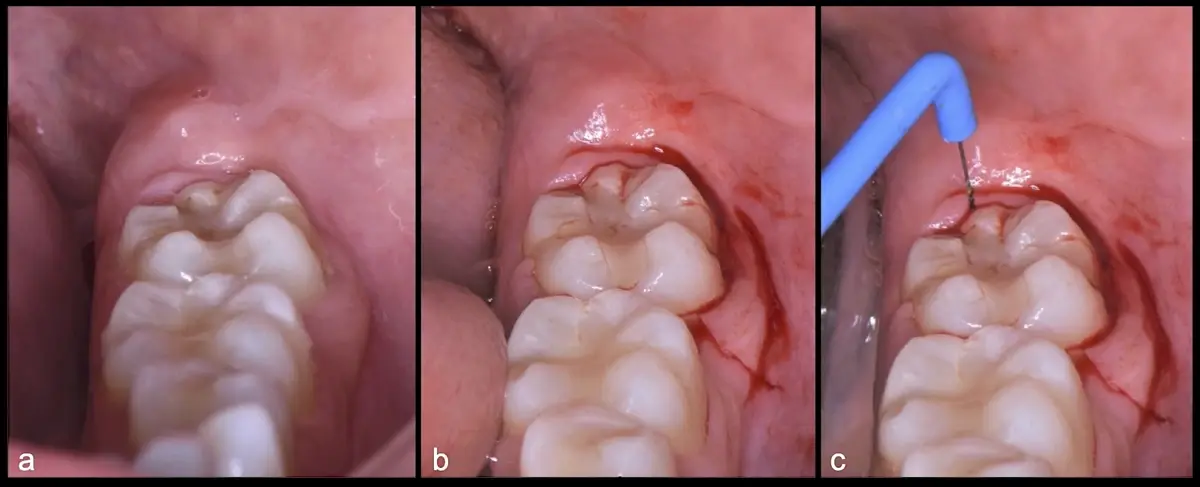

Figura 15. Vista clínica de la pieza 3.8 retenida (a). Incisión intrasulcular vestibular y distal e incisión vertical por mesial de 3.7 (b). Incisión horizontal en dirección distal de la pieza 3.7 con punta de corte del electro bisturí (c).